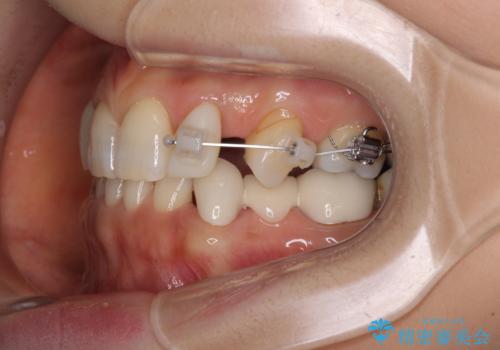

上顎は左右ともに小臼歯が欠損しており、右側は乳前歯が残っている状態でした。

ブリッジによる補綴治療にて、欠損や隙間を補完することとしましたが、神経を取り除いたり、審美的に不自然になることを避けるため、部分矯正を併用することとしました。

乳歯は事前に抜歯することとしました。